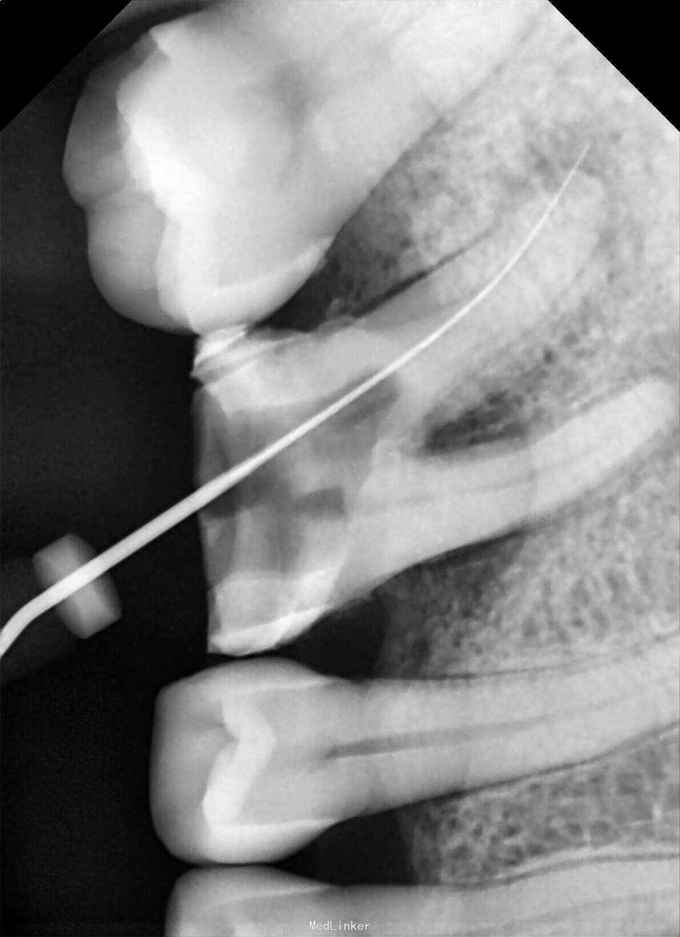

检查:36牙残冠,开髓洞型,叩(+),松(-) 辅查:36牙远中根管口有异物,根尖暗影

诊断:36牙慢性根尖周炎 治疗:36牙探及根管口④,远颊根管口阻塞,选用尖头金刚砂车针去除部分髓底,暴露断针头部,超声(P尖)逆时针振荡,直到断针松动,然后用血管钳取出断针,疏通根管,机扩,充填,术后1个月复查,根尖暗影范围略有缩小